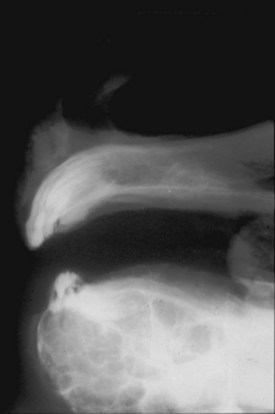

Clinical features

The condition is usually presented as a painful, hot, progressive swelling of the mandible with a characteristic ‘sun-burst’ radiographic appearance of bone lysis and irregular deposition of trabecular reactive new bone44 (Fig. 11.12). Pathological fractures can occur in affected bones.

image image image image image

Fig. 11.12 (A) & (B) This 5-year-old Irish Draught mare was presented with a 4-week history of a mandibular swelling, gingival bleeding, weight loss and dysmasesis. The mandibular incisors were palpably loose and the mandible was warm to the touch and mildly painful on palpation. (C) & (D) Lateral and occlusive radiographs gave the suspicion of a neoplastic lesion. (E) A bone biopsy was taken from several sites, and the horse was diagnosed with osteosarcoma.

Diagnostic confirmation

Their radiographic appearance is highly suggestive, but biopsy provides the only definitive diagnosis. There is a characteristic combination of cortical bone destruction and periosteal new bone formation giving the area a ‘sunburst’ radiographic appearance.

Bone biopsies of osteosarcoma are sometimes easy to obtain, since the bone is usually softer than normal and the medullary cavity is filled with diagnostically significant friable pink to white material containing variable amounts of cancellous bone (Fig. 11.12E). It is easy to miss tumor tissue in small bone biopsies, and florid, non-neoplastic reactive bone or fracture callus can easily be mistaken histologically for neoplasia. Multiple biopsies should, therefore, be collected from sites identified by radiography or CT or MR imaging methods, but this is not an easy procedure.